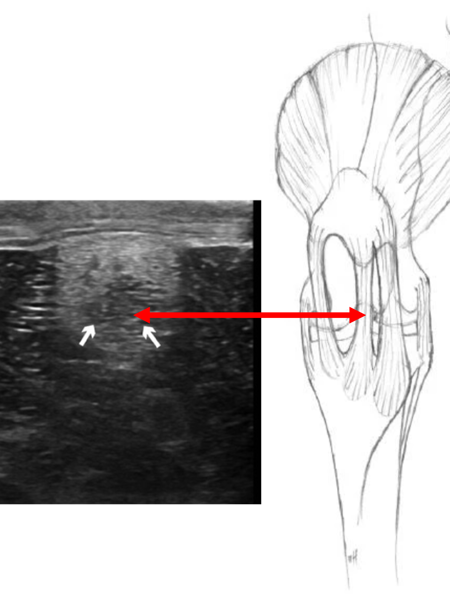

Vid hältutredningar används ofta ultraljud för att hitta skador i senor och ligament. Skadorna visar sig som mörkare partier på ultraljudsbilden, så kallade hypoechoiska områden. Från hästens knäskål finns tre stora ligament som håller knäskålen (patella) på plats som kan drabbas av skador, vilka kan upptäckas med ultraljud. Det är dock oklart om ultraljudsförändringar på ligamenten alltid är förenat med smärta och hälta. Kan dessa förändring finnas hos hästar som tränas utan att de ger några symtom på sjukdom?

Ultraljudsundersökningarna visade att dessa hypoechoiska områden i patellarligamenten, det vill säga mörkare partier som tyder på skador i senor och ligament i hästens knäskål, var vanligt förekommande även hos hästar utan symtom och i fullt arbete. Förändringarna sågs i alla tre ligamenten, men de var vanligast i det mellersta patellarligamentet och sågs hos 20 procent av hästarna. På gruppnivå fanns inget samband mellan fynden och grad av asymmetri eller hälta från rörelseanalyserna.

Resultaten tyder på att hypoechoiska ultraljudsförändringar inte nödvändigtvis är tecken på skada. Det skulle kunna vara en normal variation, en fysiologisk anpassning till belastning eller en äldre skada som läkt. Det är därför viktigt att ultraljudsfynd alltid tolkas i kombination med en klinisk undersökning och bedövning för att se om de har en klinisk betydelse eller inte.